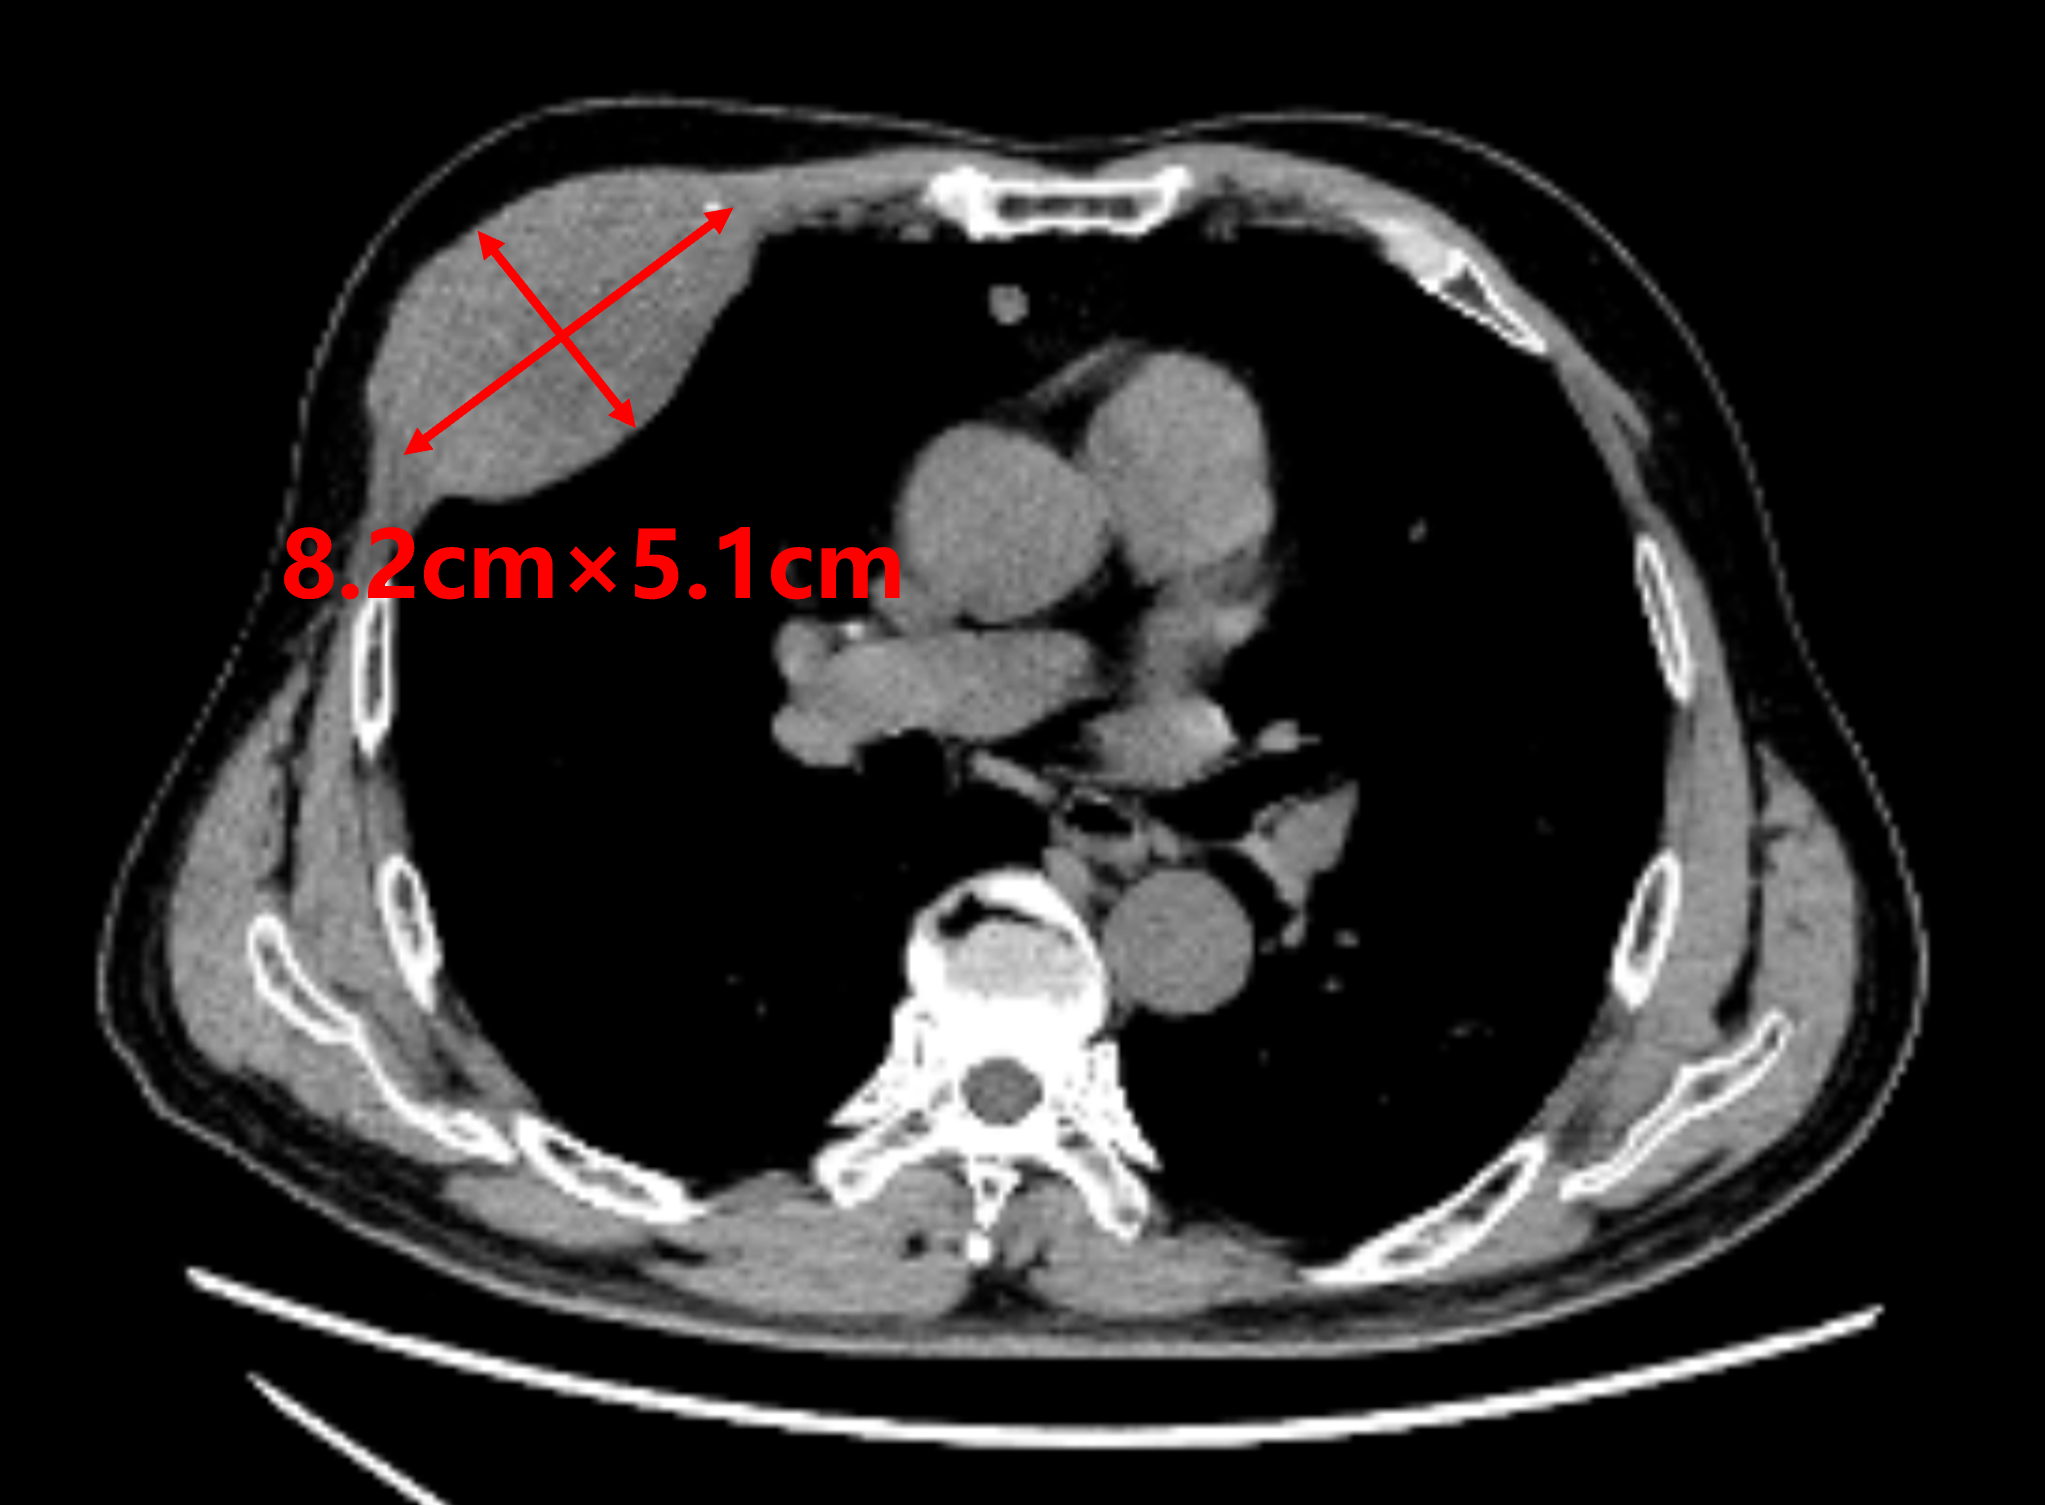

患者1年前罹患原发性肝癌,经多学科综合治疗后肝内肿瘤控制稳定,但近期出现右胸壁局部疼痛不适,严重影响睡眠等日常生活。进一步检查发现右第4前肋骨骨质破坏伴软组织肿块形成,大小约8.2cm×5.1cm,提示为肝癌右胸壁转移。